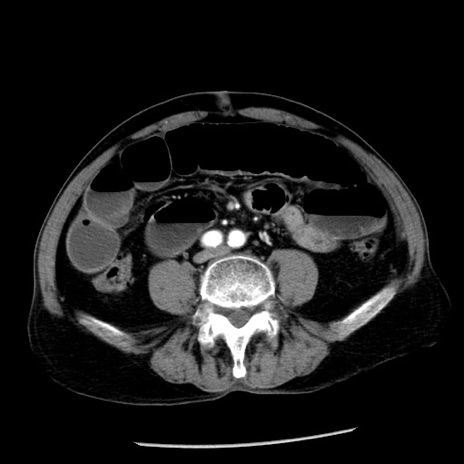

症例26(横断像)

【症例】80歳代男性

【主訴】嘔吐

【現病歴】昨晩2回嘔吐あり、今朝になっても嘔吐あり。来院。

【既往歴】胃潰瘍

【身体所見】意識清明、BT 37.6℃、BP 166/95mmHg、HR 100bpm、SpO2 97%、腹部:平坦・軟、腸蠕動音聴取良好、圧痛なし。

【データ】WBC 21900、CRP 1.46